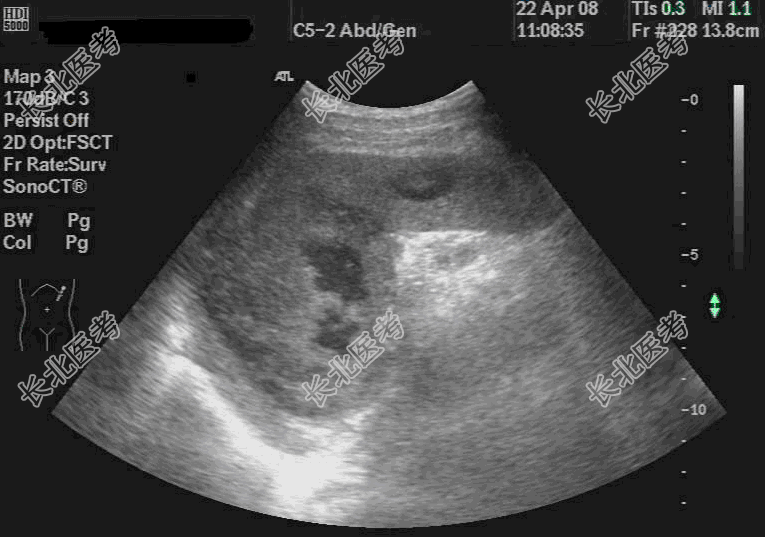

- 单项选择题患者男,77岁, 由于“间断发热半月余,加重伴胸闷1天”来诊, 曾间断使用头孢三代、喹诺酮类等抗炎及退热药物治疗,未见明显好转。入院体格检查: 体温39.1℃,脉搏88次/分, 呼吸22次/分,双肺听诊: 呼吸音减低,未闻及干湿啰音, 脾肋下未及,肝肾区无叩痛, 上腹正中有压痛。辅助检查:血常规WBC 21.2×109/L, N 85.6%,L6.9%; 超声检查如图,应诊断为

C、脾多发性脓肿